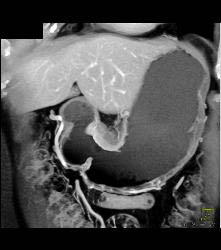

GIST Tumor